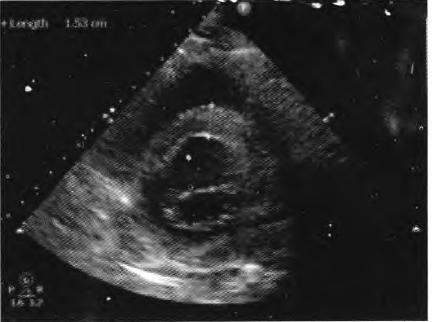

患者择期于10月25日行冠状动脉介入治疗,术前常规给予地塞米松10 mg静脉注射,右侧桡动脉穿刺告捷后,经鞘管送多功能造影导管至主动脉窦部,对比剂选择碘帕醇(商品名:碘必乐),导管“吾烟”后数秒钟,患者血压骤然降低至50/30 mmHg,心率逐步增快至90次/min左右,予羟乙基淀粉130/0.4氯化钠注射液(万汶)加压快速静脉滴注100 mL,反复3次静脉注射多巴胺3 mg,血压65/40 mmHg左右,约3 min后心率降至40次/min左右,监护示室性逸搏心律,继之心跳、呼吸骤停。持续胸外按压,气管插管机械通气,持续静脉泵入肾上腺素0.2仙g/(kg•min),并间断4次静脉注射肾上腺素0.5 mg,血压维持在105/50 mmHg左右,进一步行左室造影,见图1。以及左冠状动脉造影,见图2。氧饱和度降至75%,斟酌对比剂致高敏反应,引起过敏性休克,静脉滴注甲泼尼龙500mg,经右侧股动脉路径行主动脉内球囊反搏术(intra.aortic balloon pump,IABP)治疗,同时联系外科、麻醉科、体外循环科经左侧股动脉一股静脉行体外膜肺氧合(extra—corporeal membrane oxygenation,EC—MO)支持治疗。ECMO置人后将患者由导管室转送至冠心病监护病房(coronary care unit,CCU)继续抢救治疗,床边心脏超声,见图3。提示室间隔水肿(厚度1.53 cm)。在置人ECMO初期维持绝对镇静,下调直至停用血管活*药性**物,心律以室性逸搏心律为主(持续约48 h),偶然有室速、室颤发作,未作处理。在置人ECMO第3天因急性肾衰竭行床旁连续静脉静脉血液滤过(continuous veno—venous hemofiltration,CVVH)治疗,第4天后患者心率、血压稳定,复查心脏超声提示左心室射血分数40%,撤除ECMO,此后依次拔除气管插管、撤除IABP以及停止CVVH等治疗,患者恢复良好,于11月14日出院。

图3心脏超声提示室间隔水肿,厚度1.53 cm